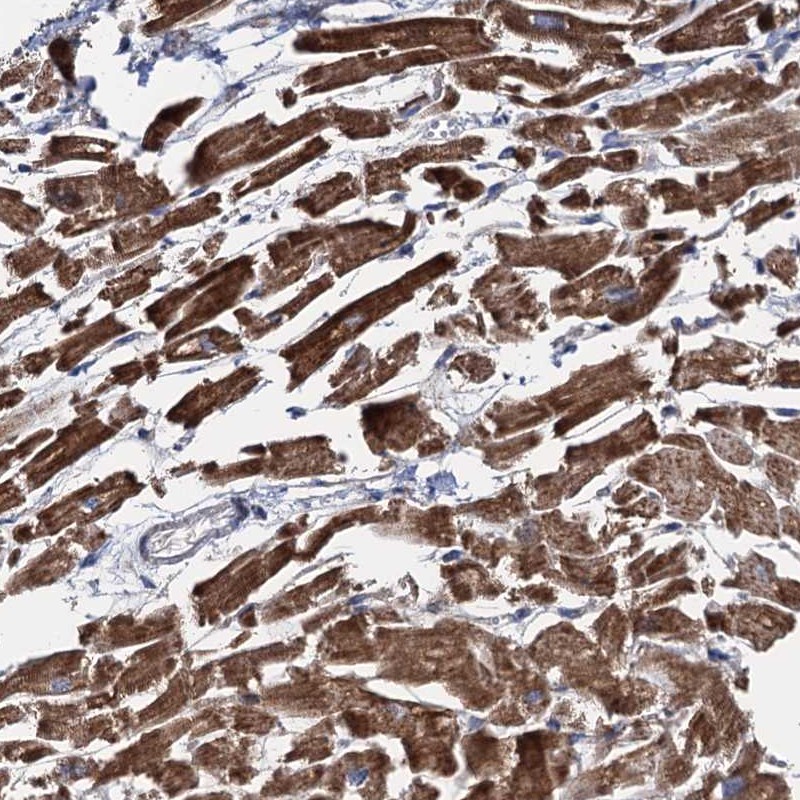

Immunohistochemical staining of human heart muscle shows distinct cytoplasmic positivity in myocytes.